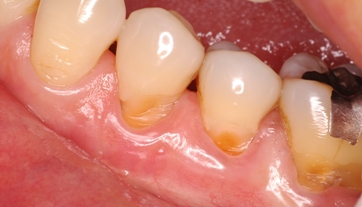

4bd892d4.jpgまずこれ 楔状欠損という

歯の根元が削れる 高度の圧力が歯にかかり歯が耐えられないのである

木こりが木の根元を斧で切るように、根元が楔状に削れるのである